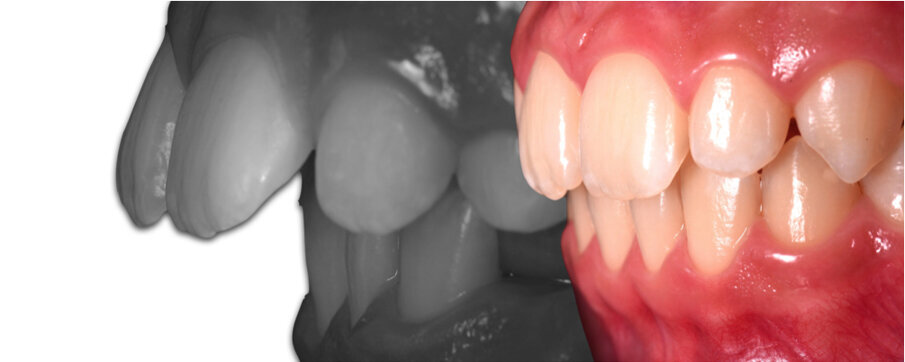

Caso 1 Paziente di anni 9,5, II Classe scheletrica, retrusione mandibolare, contrazione dell’arcata superiore, Overjet elevato (9,5 mm), compressione delle vertebre cervicali. La paziente riferisce di soffrire di cefalee continue. Dall’esame della panoramica e della teleradiografia evince una grande discrepanza tra il condilo dx e sx ed un evidente riduzione dello spazio intervertebrale in corrispondenza delle prime vertebre cervicali. La paziente è sottoposta a terapia elastodontica con AMCOP di seconda classe SC 3 con lo scopo di favorire l’espansione dell’arcata superiore e l’avanzamento mandibolare. A distanza di un anno evince un miglioramento dell’articolazione temporo-mandibolare di sx ed un aumento dello spazio intervertebrale legato a l’avanzamento mandibolare, è evidente inoltre il miglioramento dell’overbite ed overjet. A distanza di 2 anni si assiste ad un netto miglioramento dei condili grazie all’azione scheletrica dell’AMCOP ed a un netto vantaggio posturale con aumento dello spazio tra le vertebre cervicali. La malocclusione si può dire risolta anche se necessita una stabilizzazione del caso clinico attraverso lo stesso dispositivo (Figg. 2-14).